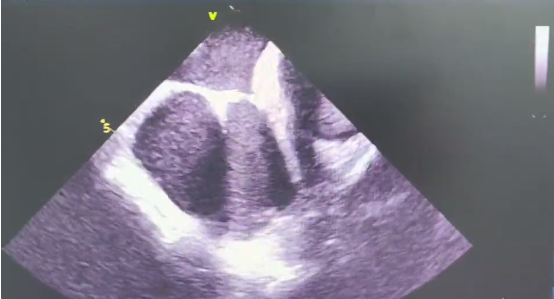

在术前评估中,陈弹主任团队通过CT建模发现患者左心房内疑似存在心房隔膜。术中通过心腔内超声进一步检查,明确了患者左心房内部的确存在心房隔膜,而心房隔膜的存在增加了术中导管操作的难度。在我院心内科电生理团队的共同努力下,房颤一站式手术顺利完成。在肺静脉隔离过程中,患者房颤心律成功转复为窦性心律。困扰了吴爷爷3年多的“心病”得以解决。